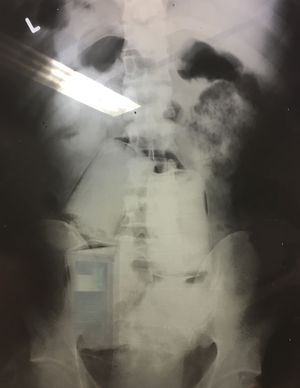

At the airport the police had taken a patient to us accused having drugs with him. After an Xray we could see 4 packets of cocaine which had been swallowed before the flight . This kind of drug smuggling is called bodypacking.